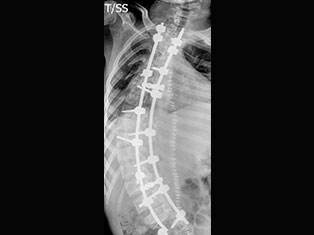

Degenerative Spine

The phrase "degenerative changes" in the spine refers to osteoarthritis of the spine. Osteoarthritis is the most common form of arthritis. Doctors may also refer to it as degenerative arthritis or degenerative joint disease.